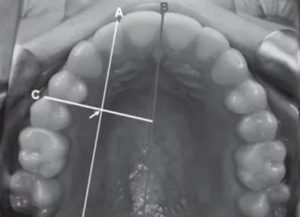

Фото

Фото 1. Воспаление надкостницы нередко возникает по причине неполного удаления осколков зуба. В этом случае требуется хирургическая операция по их извлечению.

Фото 2. Иногда после сложного удаления зуба пациенты замечают в десне торчащую кость. Возможно это экзостоз, для постановки точного диагноза рекомендуется обращаться к стоматологу.

Фото 3. Возле лунке, заполненной сгустком крови, отчетливо видно кость. В данном случае это может быть ранее незамеченный врачом обломок зуба, челюстная кость или сверхкомлектный зуб.